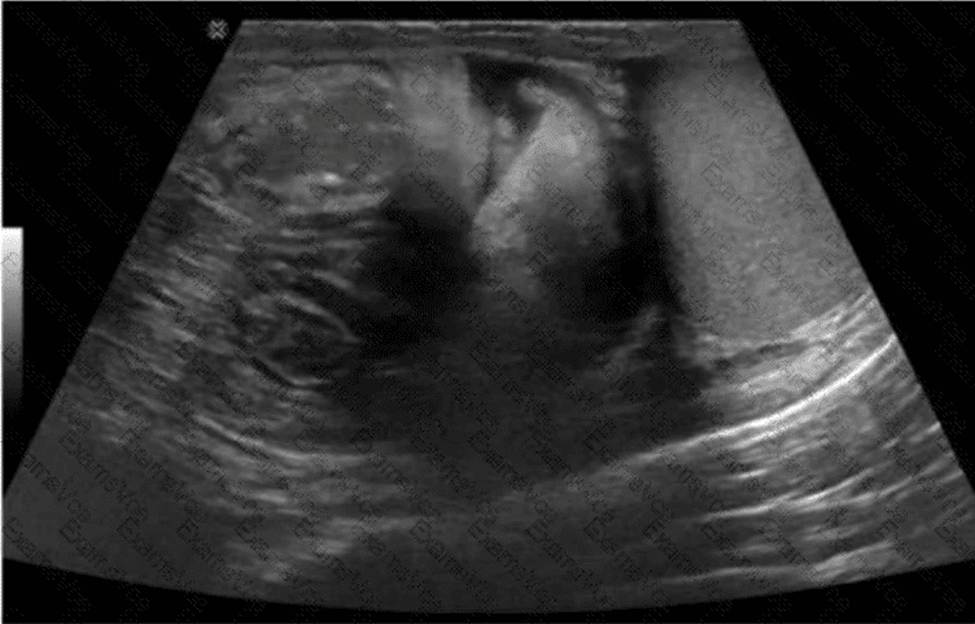

Which condition is demonstrated in this image of the groin?

The ultrasound image demonstrates bowel loops with peristalsis visualized within the inguinal canal, which is diagnostic of an inguinal hernia―more specifically, an indirect inguinal hernia. Indirect hernias pass through the deep inguinal ring and may extend into the scrotum, appearing sonographically as bowel-containing masses adjacent to or within the scrotal sac. Peristaltic motion confirms the presence of viable bowel content.

This finding is typical in indirect inguinal hernias, which are more common in males and often congenital due to a patent processus vaginalis. The herniated bowel can be traced through the inguinal canal, as seen in this image.

Comparison of answer choices:

A. Hematocele presents as a complex fluid collection surrounding the testis, often due to trauma―no complex fluid or trauma is apparent here.

B. Testicular rupture shows discontinuity of the tunica albuginea and irregular testicular contour―none of which is seen.

C. Orchiectomy would show an absent testis―this is not the case here.

D. Indirect hernia is correct. The presence of bowel with peristalsis in the inguinal canal is diagnostic.